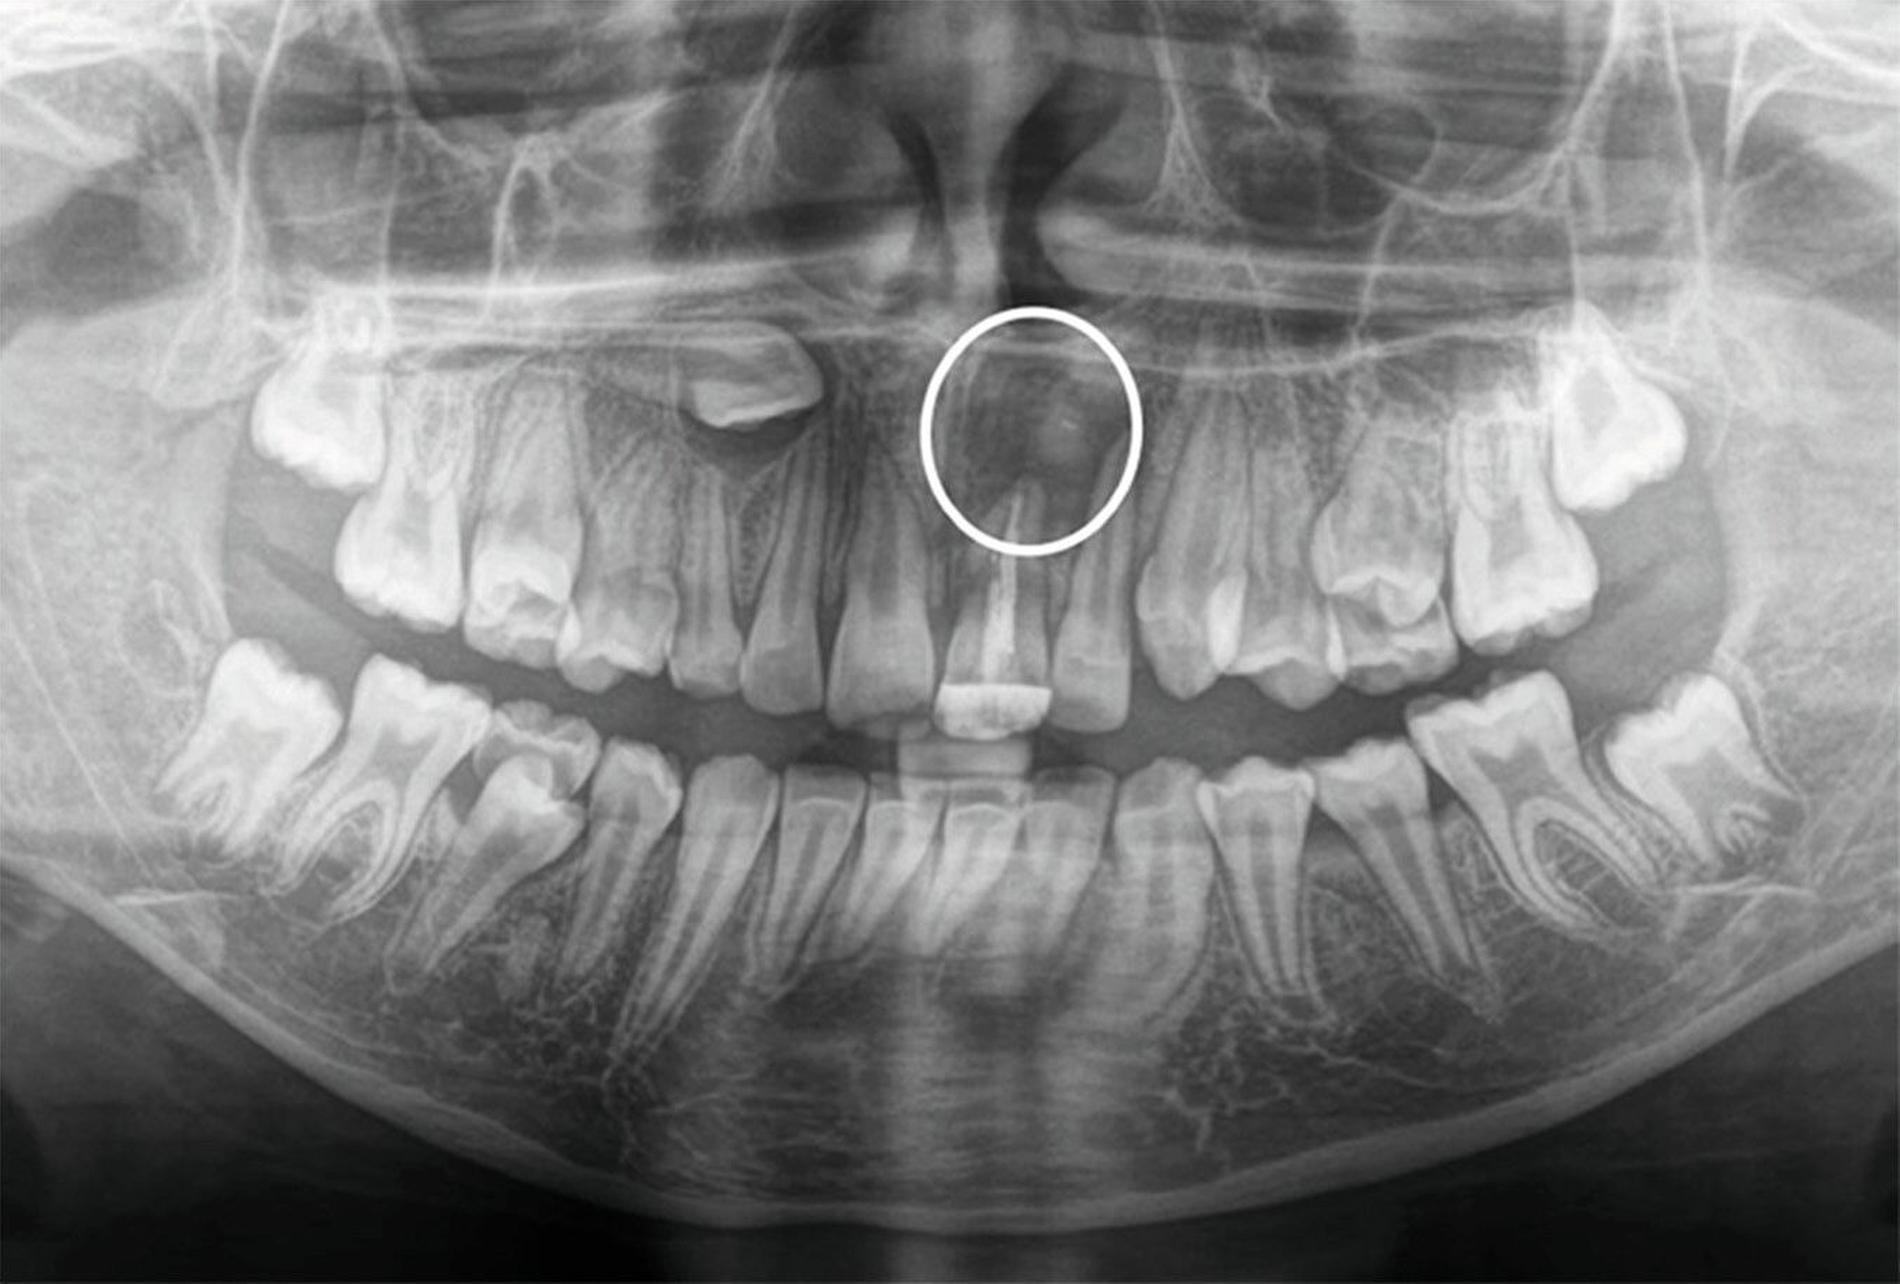

Zwei Jahre nach einem komplexen Zahntrauma mit komplizierter Kronenfraktur 21 und endodontischer Versorgung stellte sich eine elfjährige Patientin mit nun ausgedehnter apikaler Beherdung am Zahn 21 bei uns vor (Abbildung 1). In ihrer Krankengeschichte hatte die Patientin im Alter von vier Jahren eine Leukämie überwunden. Es wurden keine weiteren gesundheitlichen Probleme angegeben. Im OPG zeigt der Zahn 21 eine periapikale Aufhellung im Sinne einer Parodontitis apicalis chronica mit nun akuten klinischen Schmerzen (Abbildung 1).

Zur weiteren Abklärung wurde eine dreidimensionale Aufnahme durchgeführt (DVT). Dabei bestätigte sich die erhebliche Osteolysezone im apikalen Bereich des vormals traumatisierten Zahnes 21. Der Zahn 13 stellt sich hoch verlagert am Nasenboden dar, während es bei dem persistierenden Milchzahn 53 zu einem natürlichen Lückenschluss in regio 13 gekommen ist (Abbildung 2).